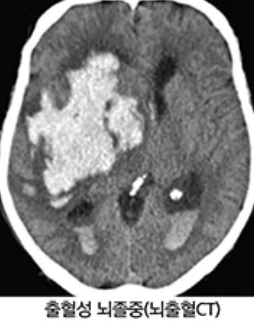

1) 전산화단층촬영(CT 스캔)

뇌의 구조와 혈액 순환이 어떻게 이루어지는지를 확인하기 위해 사용됩니다. CT 스캔은 X선을 사용하여 뇌의 단면 이미지를 생성합니다.